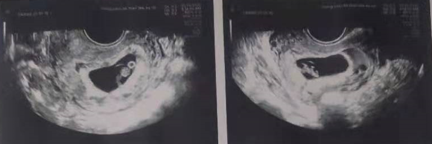

8月份,内膜准备我走的是自然周期,移植1枚囊胚,11天后到医院抽血验得好孕!